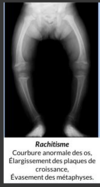

Perfectly

12

Q

A

Maintien de la matrice Sont entourés de matériel intercellulair ecalcifié INCAPABLE de se diviser